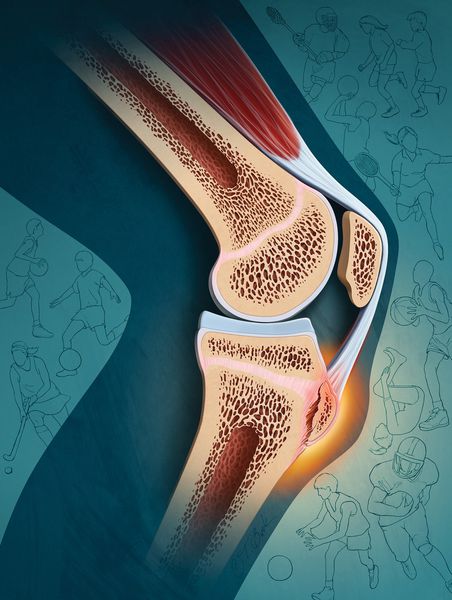

Патогенез болезни Осгуда — Шляттера

Бугристость большеберцовой кости представляет собой перевернутый треугольник, к которой крепится связка надколенника — продолжение сухожилия прямой мышцы бедра (части четырёхглавой мышцы) [8] [9] .

Когда сгибается коленный сустав, прямая мышца бедра напрягается и укорачивается, а связка надколенника тянет ткань, окружающую кость (надкостницу), в месте своего прикрепления — бугристости большеберцовой кости, после чего у подростка появляется отёк и тупая боль под коленным суставом, которая усиливается при активности.

Из-за постоянных микротравм обрывается много капилляров, но кровоснабжение в большеберцовой кости не нарушается. Это приводит к кровоизлиянию, и у пациентов появляются синяки диаметром 1–3 см. Если не прекратить тренировки, начинается отрыв надкостницы вместе с костным фрагментом (апофизом). На месте отрыва формируется костная мозоль и бугристость становится заметной [10] [12] .